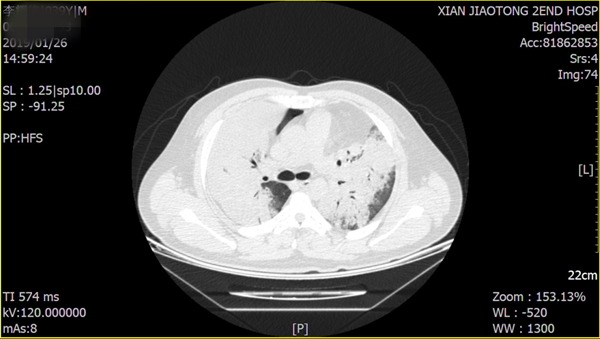

患者的胸部CT影像